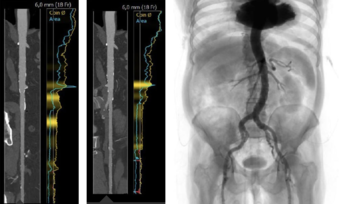

- Learn why and how cardiac CT is playing an increasingly important role in the evaluation of patients with severe aortic stenosis (e.g., calcium score, coronary evaluation)

Good to know: this webinar will reveal the treatment strategy of the case: “Interdisciplinary therapeutic strategy in a low‑risk patient with aortic stenosis and preserved life expectancy”.

Enhance your learning experience by consulting the clinical case that will be up for discussion: "Interdisciplinary therapeutic strategy in a low-risk patient with aortic stenosis and preserved life expectancy". How would you treat?

This PCR Webinar focused on the case "Interdisciplinary therapeutic strategy in a low‑risk patient with aortic stenosis and preserved life expectancy".